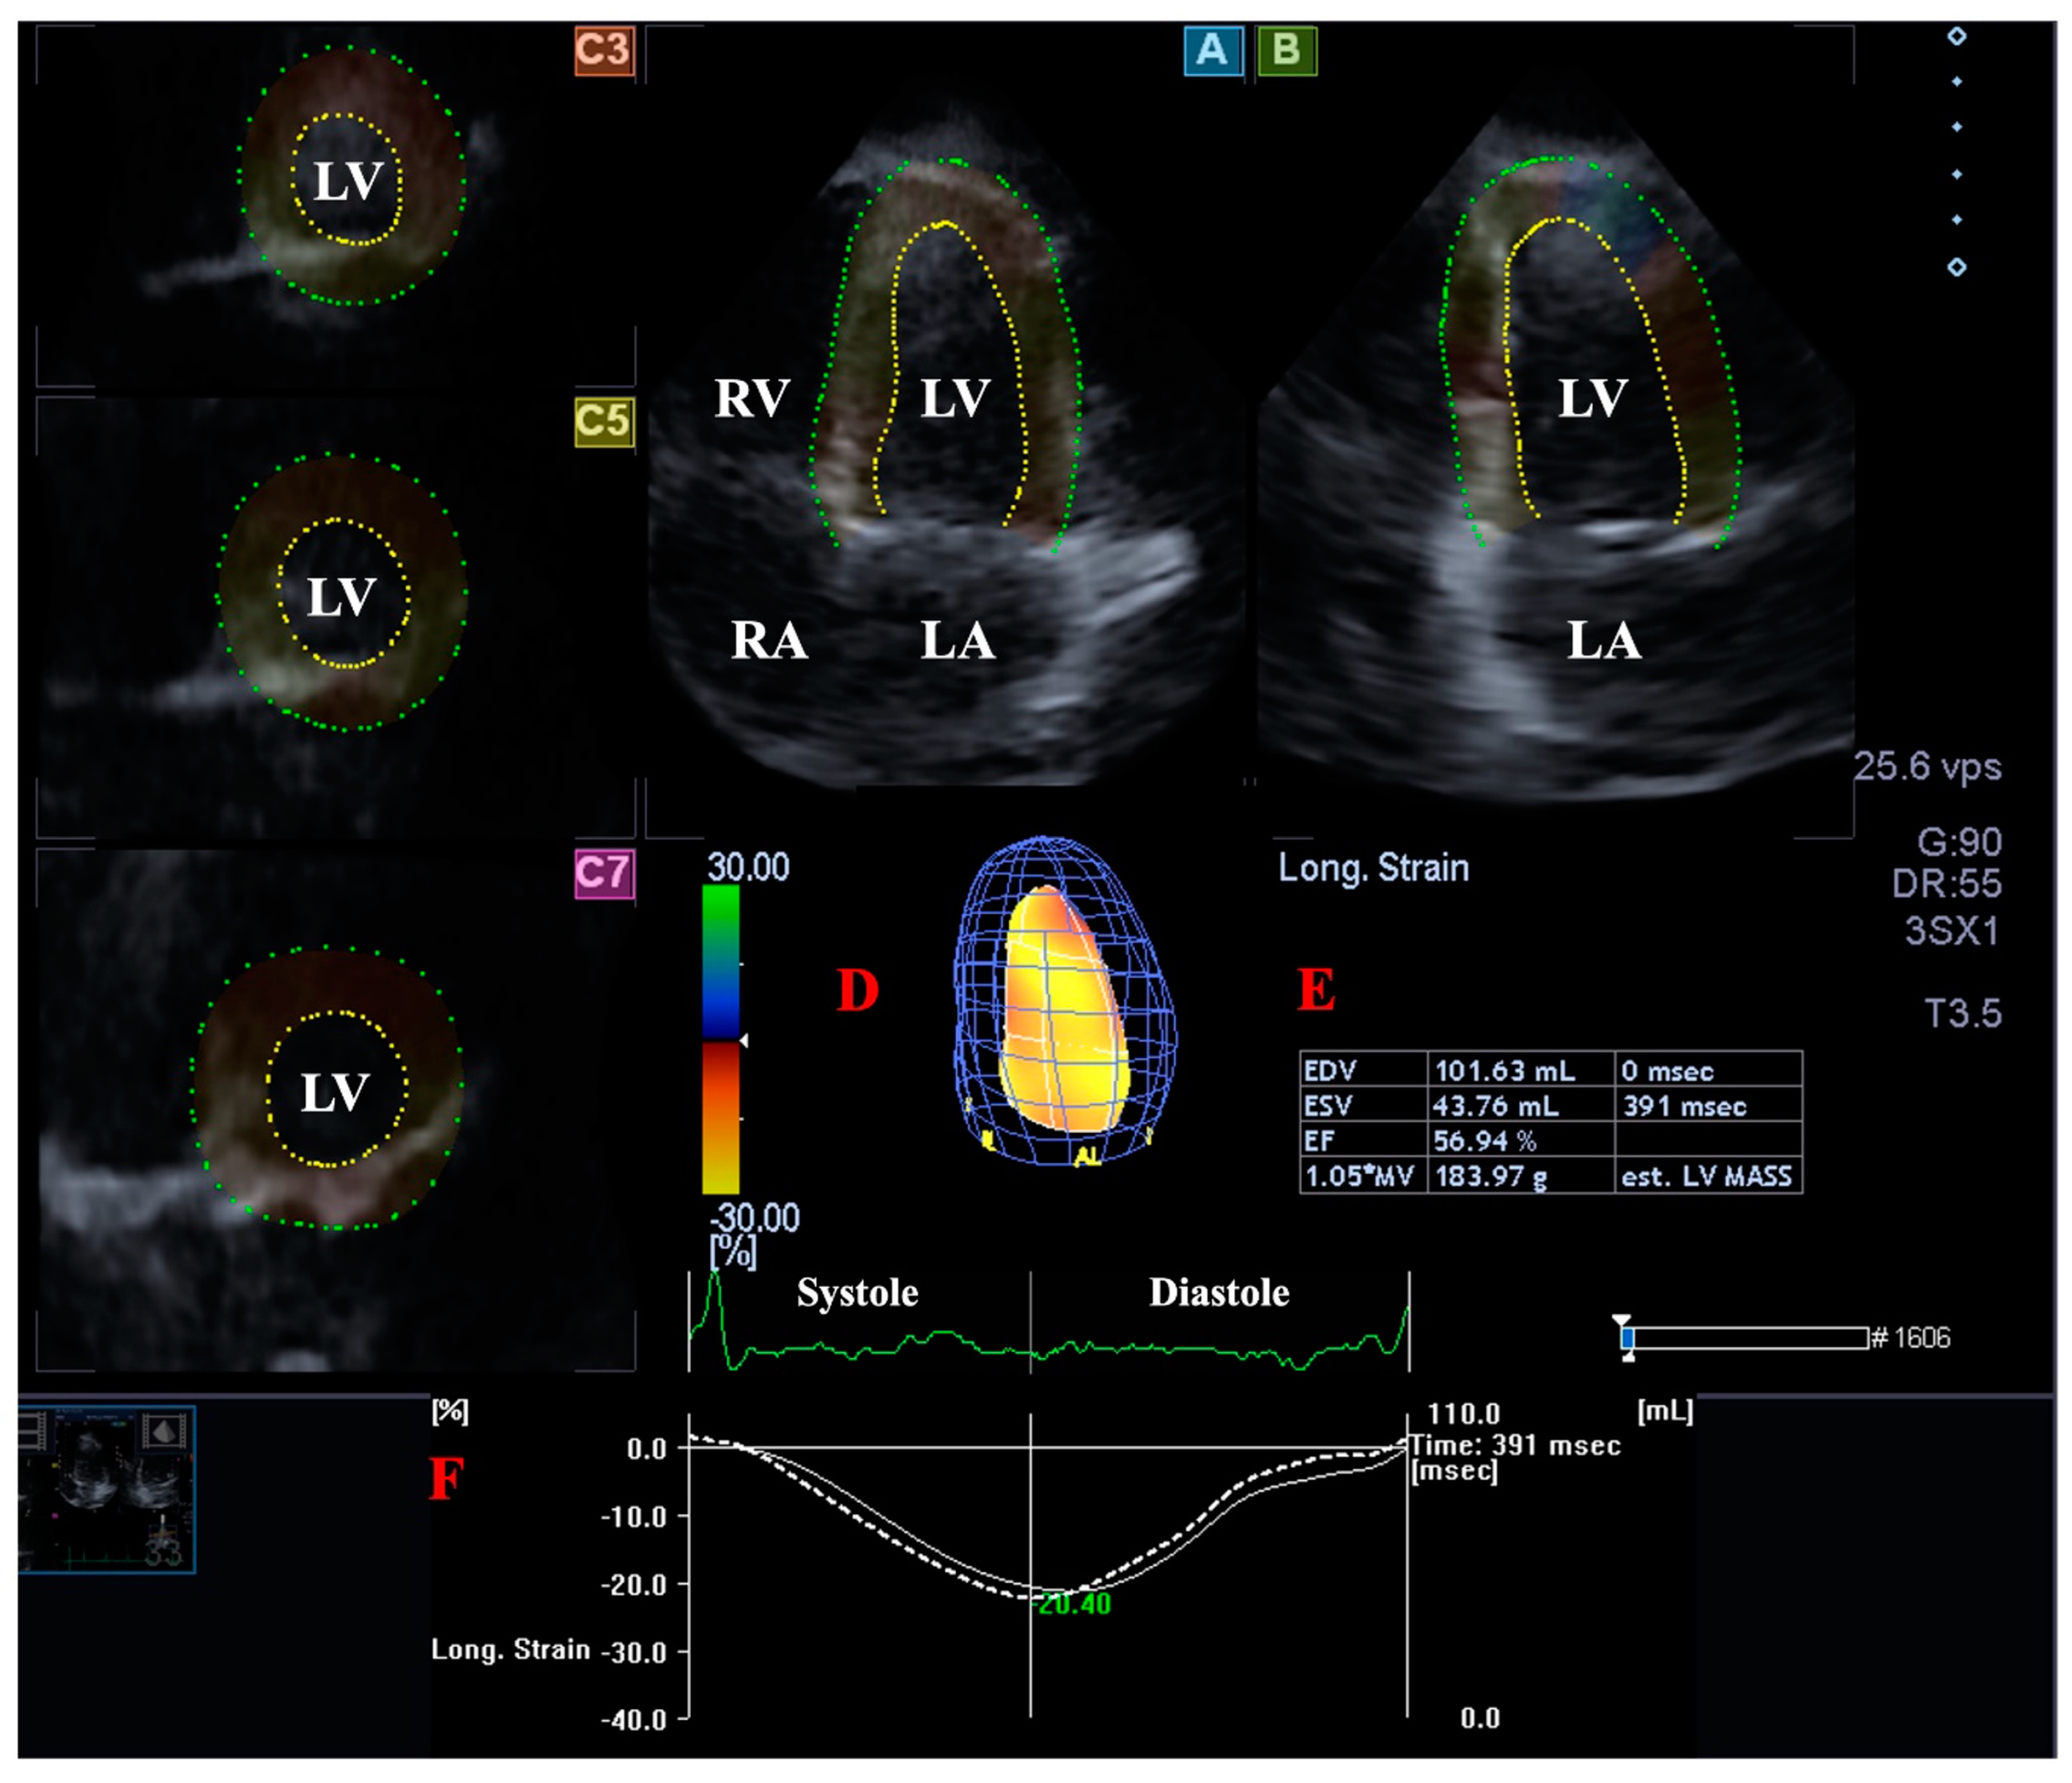

Using the above mentioned software, data were presented in optimal apical longitudinal 4-chamber (AP4CH) and 2-chamber (AP2CH) views, and basal, midventricular, and apical cross-sectional views focused on the LV. Following definition of mitral annular (MA)–LV edges and endocardial surface of the LV apex, sequential analysis was performed proceeding into the creation of a virtual 3D LV cast (Figure 1). Using this LV model, end-systolic (ESV) and end-diastolic (EDV) LV volumes, LV ejection fraction (E-Fr), and LV mass were determined [4,5,6,7,11].

Figure 1.

Three-dimensional (3D) speckle-tracking echocardiography-derived left ventricular (LV) volumetric analysis. Apical four-chamber view (A); apical two-chamber view (B); short-axis view at basal (C3), midventricular (C5), and apical LV level (C7) are demonstrated together with a 3D cast of the LV (D) and calculated LV volumetric data (E). Time-global LV longitudinal strain curve (white line) and time-LV volume change curve (dashed white line) are shown as well (F). Abbreviations. LA: left atrium, LV: left ventricle, RA: right atrium, RV: right ventricle, EDV: end-diastolic volume, ESV: end-systolic volume, EF: ejection fraction.